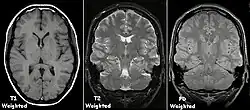

Examples of T1-weighted, T2-weighted and PD-weighted MRI scans

Each tissue returns to its equilibrium state after excitation by the independent relaxation processes of T1 (spin-lattice; that is, magnetization in the same direction as the static magnetic field) and T2 (spin-spin; transverse to the static magnetic field). To create a T1-weighted image, magnetization is allowed to recover before measuring the MR signal by changing the repetition time (TR). This image weighting is useful for assessing the cerebral cortex, identifying fatty tissue, characterizing focal liver lesions, and in general, obtaining morphological information, as well as for post-contrast imaging. To create a T2-weighted image, magnetization is allowed to decay before measuring the MR signal by changing the echo time (TE). This image weighting is useful for detecting edema and inflammation, revealing white matter lesions, and assessing zonal anatomy in the prostate and uterus.

The standard display of MRI images is to represent fluid characteristics in black and white images, where different tissues turn out as follows:

Signal T1-weighted T2-weighted

High

Inter- mediate Gray matter darker than white matter[15] White matter darker than grey matter[15]

Low